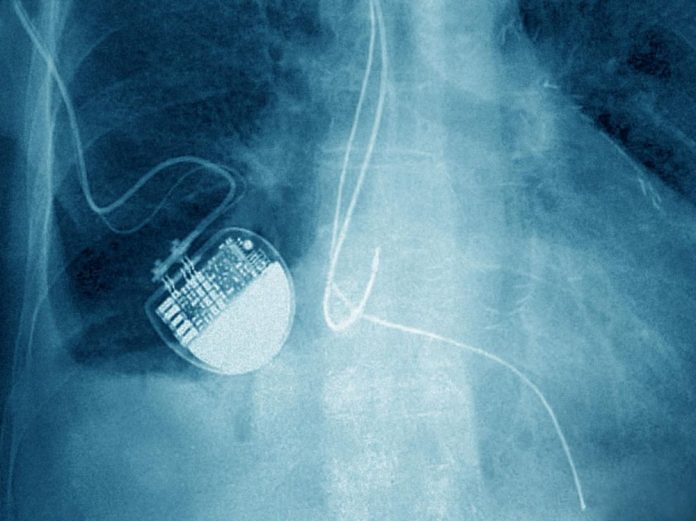

Une enquête internationale vient alerter l’opinion sur un nombre d’accidents liés à des implants médicaux anormalement élevé. Des chiffres qui seraient encore sous-estimés.

À travers le monde, 1.700.000 blessés et plus de 80.000 morts seraient recensés chaque année à cause de la pose d’un implant, et ce, sur les 10 dernières années.